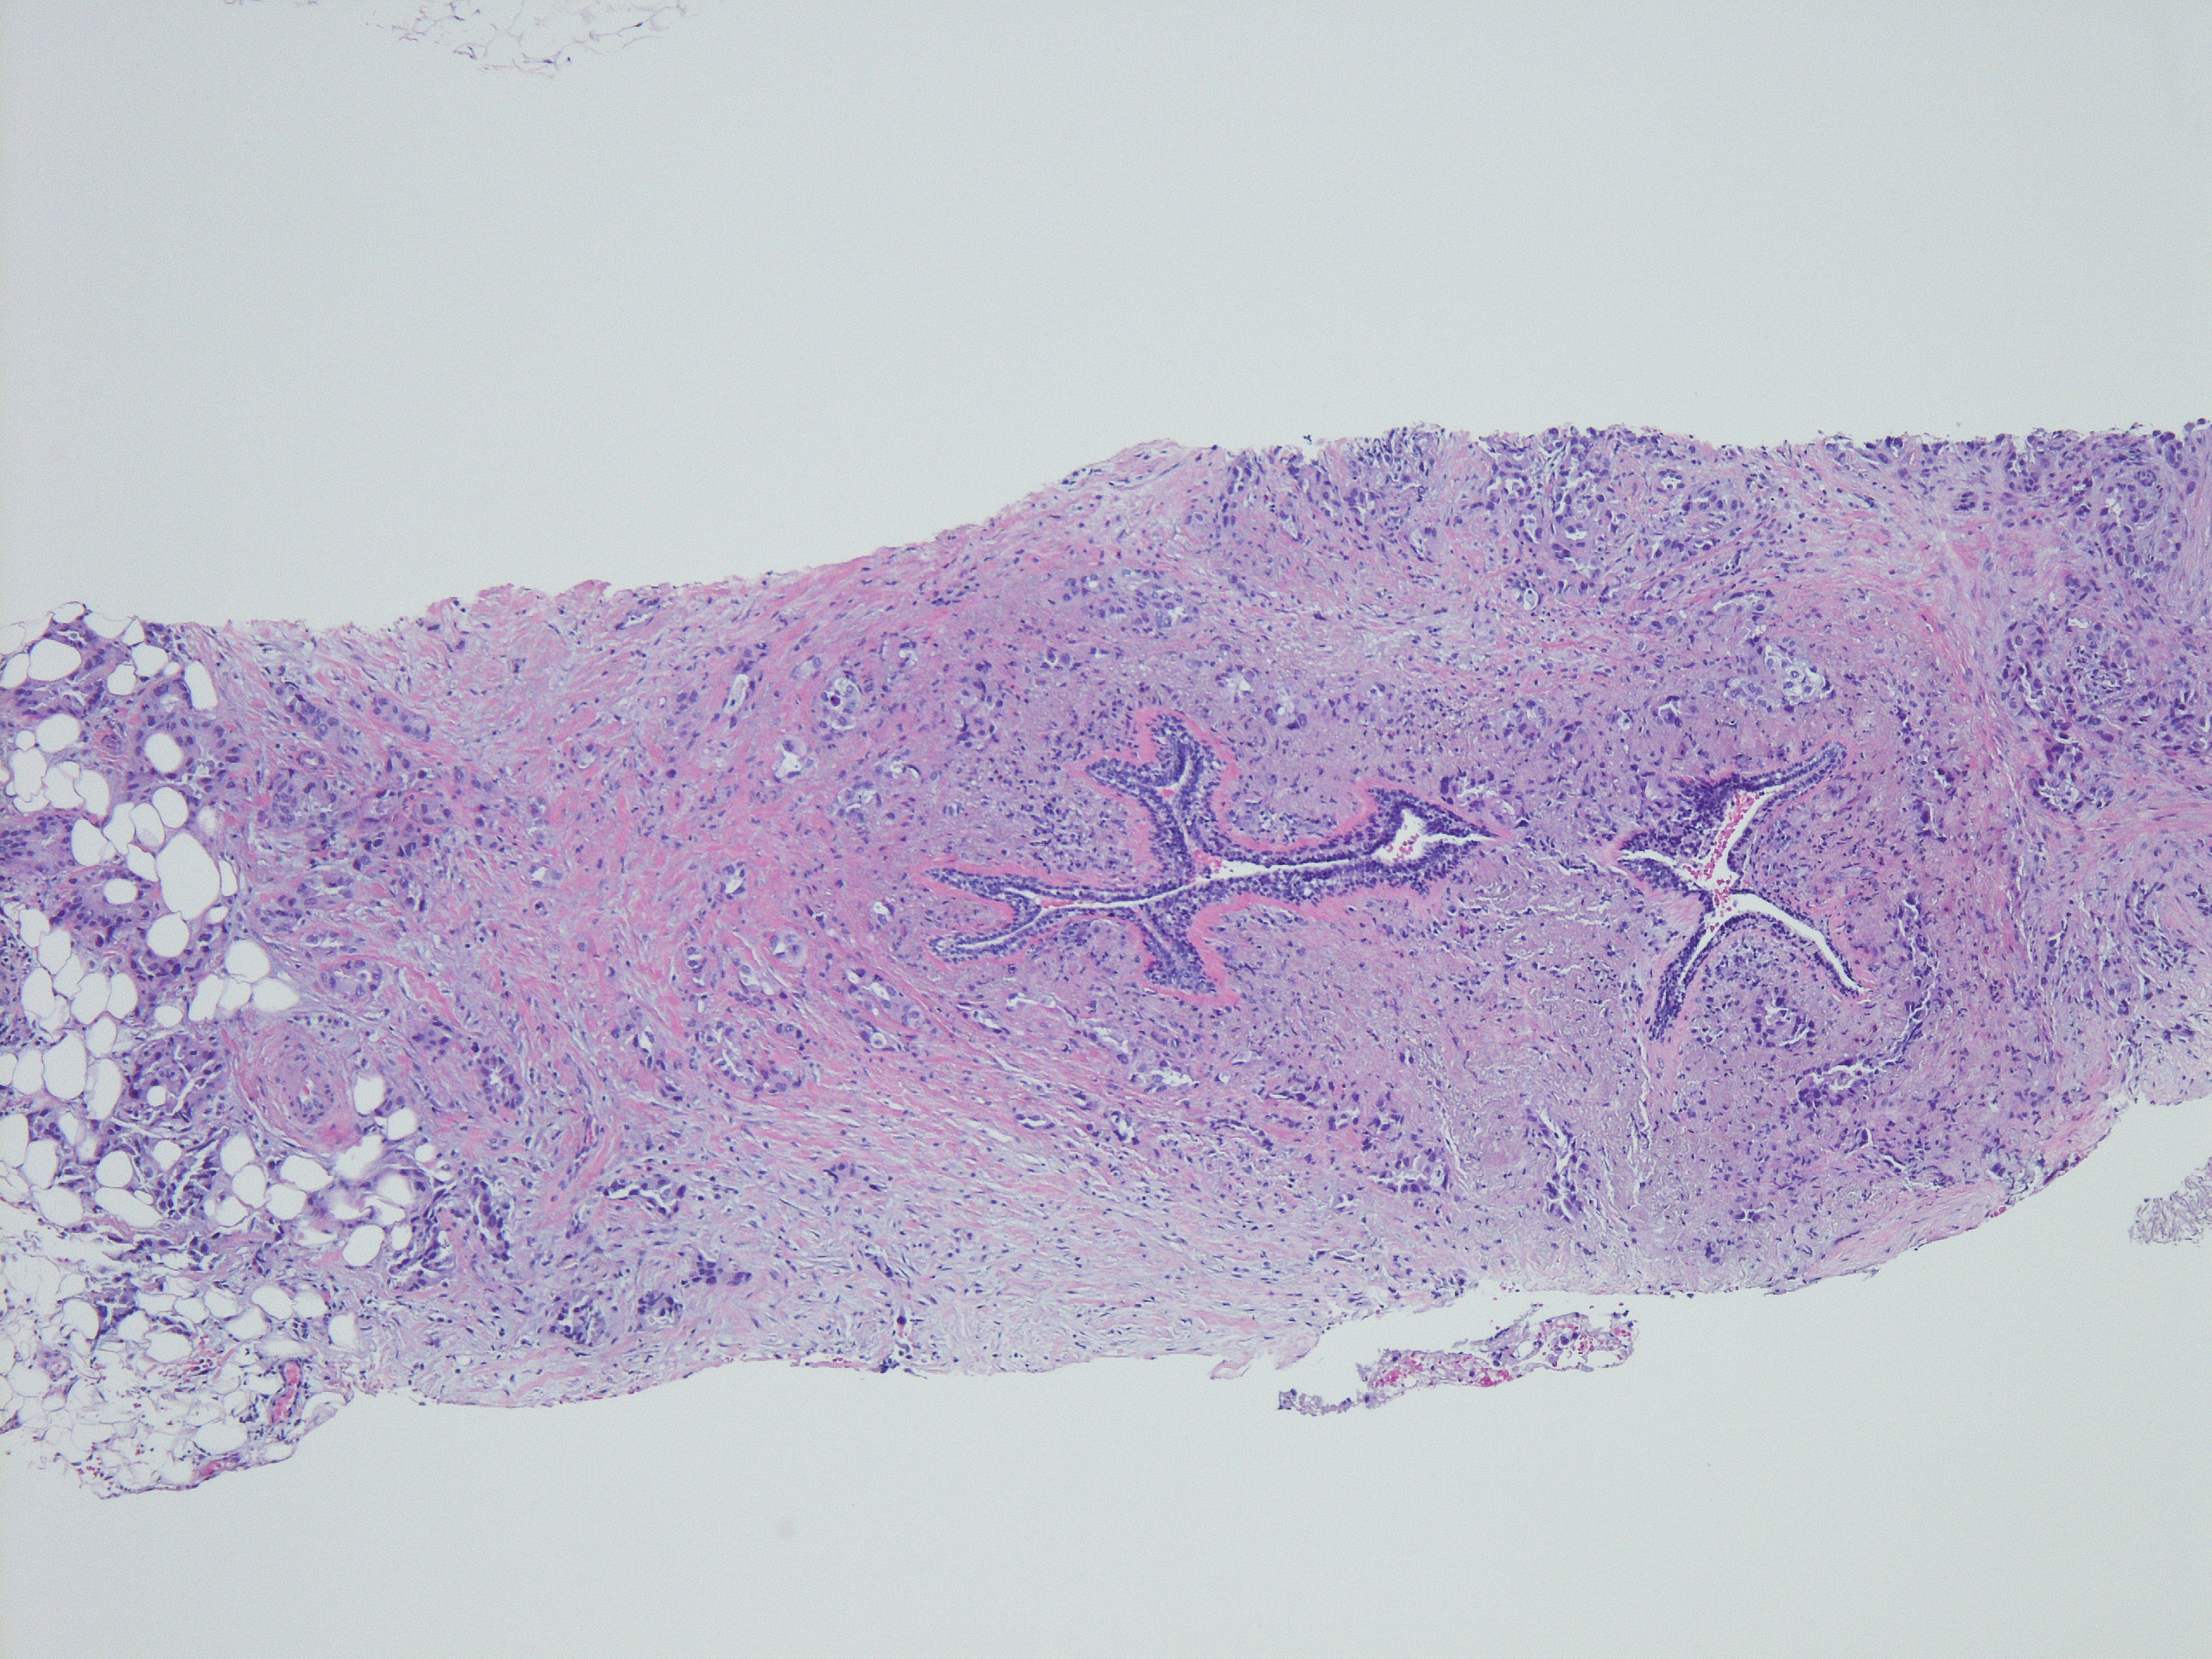

分享赵老师的一个病例:女,70岁,发现左侧乳腺肿块,2.5cm,行穿刺活检。无其他病史。

INVASIVE ADENOCARCINOMA, NUCLEAR GRADE 3.COMMENT:Multiple immunostains were ordered to determine it is a primary or metastatic tumor.

AddendumImmunostains were performed on the block. The tumor cells are positive for CK7, TTF-1, focally and weakly positive for ER, negative for PR and GATA-3, GCDFP, mammaglobin. The immunostain results support this is a metastatic carcinoma from pulmonary primary. This patient reportedly has metastatic adenocarcinoma of lung origin.AddendumNapsin A is positive, supporting a lung primary.

此例最后考虑是来自肺的转移性腺癌

约1/3的乳腺转移癌以乳腺肿块为首发症状,因为病人多采用全身或姑息治疗,所以穿刺诊断可以避免不必要的手术治疗。存在导管原位癌提示乳腺原发,钙化也多见于乳腺原发肿瘤(除卵巢浆液性癌)@杨鹏 淄博市妇幼保健院 群管 @车拴龙 吉林 :对于形态较特别的乳腺癌也是要提高警惕的